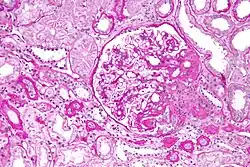

| Light micrograph of focal segmental glomerulosclerosis, hilar variant. Kidney biopsy. PAS stain. | |

On histology, FSGS manifests as scarring (sclerosis) to segments of glomeruli; moreover, only a portion of glomeruli are affected.[7][20][21] The focal and segmental nature of disease seen on histology help to distinguish FSGS from other types of glomerular sclerosis.[21]

Diagnosis of FSGS is made by renal biopsy that includes at least fifteen serial cuts with at least eight glomeruli.[32][33] Histologic features include sclerosis (scarring) of a portion (average: 15%) of the glomerular space, with only a portion of glomeruli manifesting any sclerosis.[33]

Five mutually exclusive variants of focal segmental glomerulosclerosis may be distinguished by the pathologic findings seen on renal biopsy:[35]

- Collapsing variant

- Glomerular tip lesion variant

- Cellular variant

- Perihilar variant

- Not otherwise specified (NOS) variant

Recognition of these variants may have prognostic value in individuals with primary focal segmental glomerulosclerosis. The collapsing variant is associated with higher rate of progression to end-stage renal disease, whereas the glomerular tip lesion variant has a low rate of progression to end-stage renal disease in most patients.[9] The cellular variant shows similar clinical presentation to collapsing and glomerular tip variant but has intermediate outcomes between the other two variants.[9]